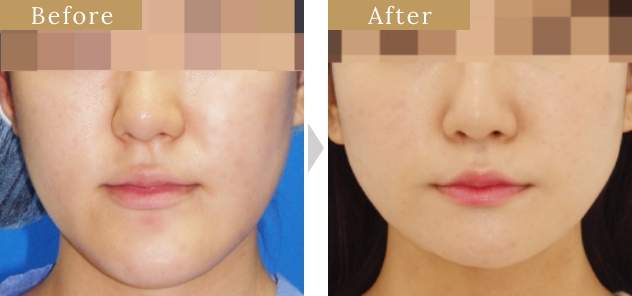

症例